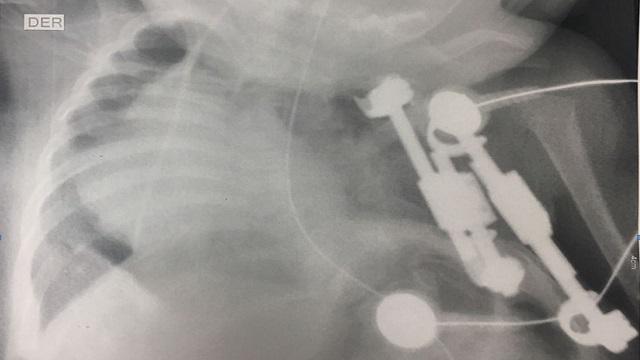

Se trata de Cristian David Morales Morales a quien le reconstruyeron la pared torácica, cuando apenas contaba con meses de nacido, mediante barras expansoras de titanio y mallas biológicas.

“La técnica que utilizamos se usa para corregir defectos pequeños, fracturas, un arco o dos, pero Cristian presentaba una ausencia casi completa. Es la primera vez que usamos este procedimiento con tal magnitud”, explicó Catalina Ramírez, médico tratante.

A pesar del pronóstico médico, la recuperación del paciente ha sido favorable y no ha presentado complicaciones. El niño continúa en seguimiento, posterior a su intervención quirúrgica, ya que se debe realizar la expansión del dispositivo a la medida del tórax cada 3 a 4 meses, acorde a su crecimiento.